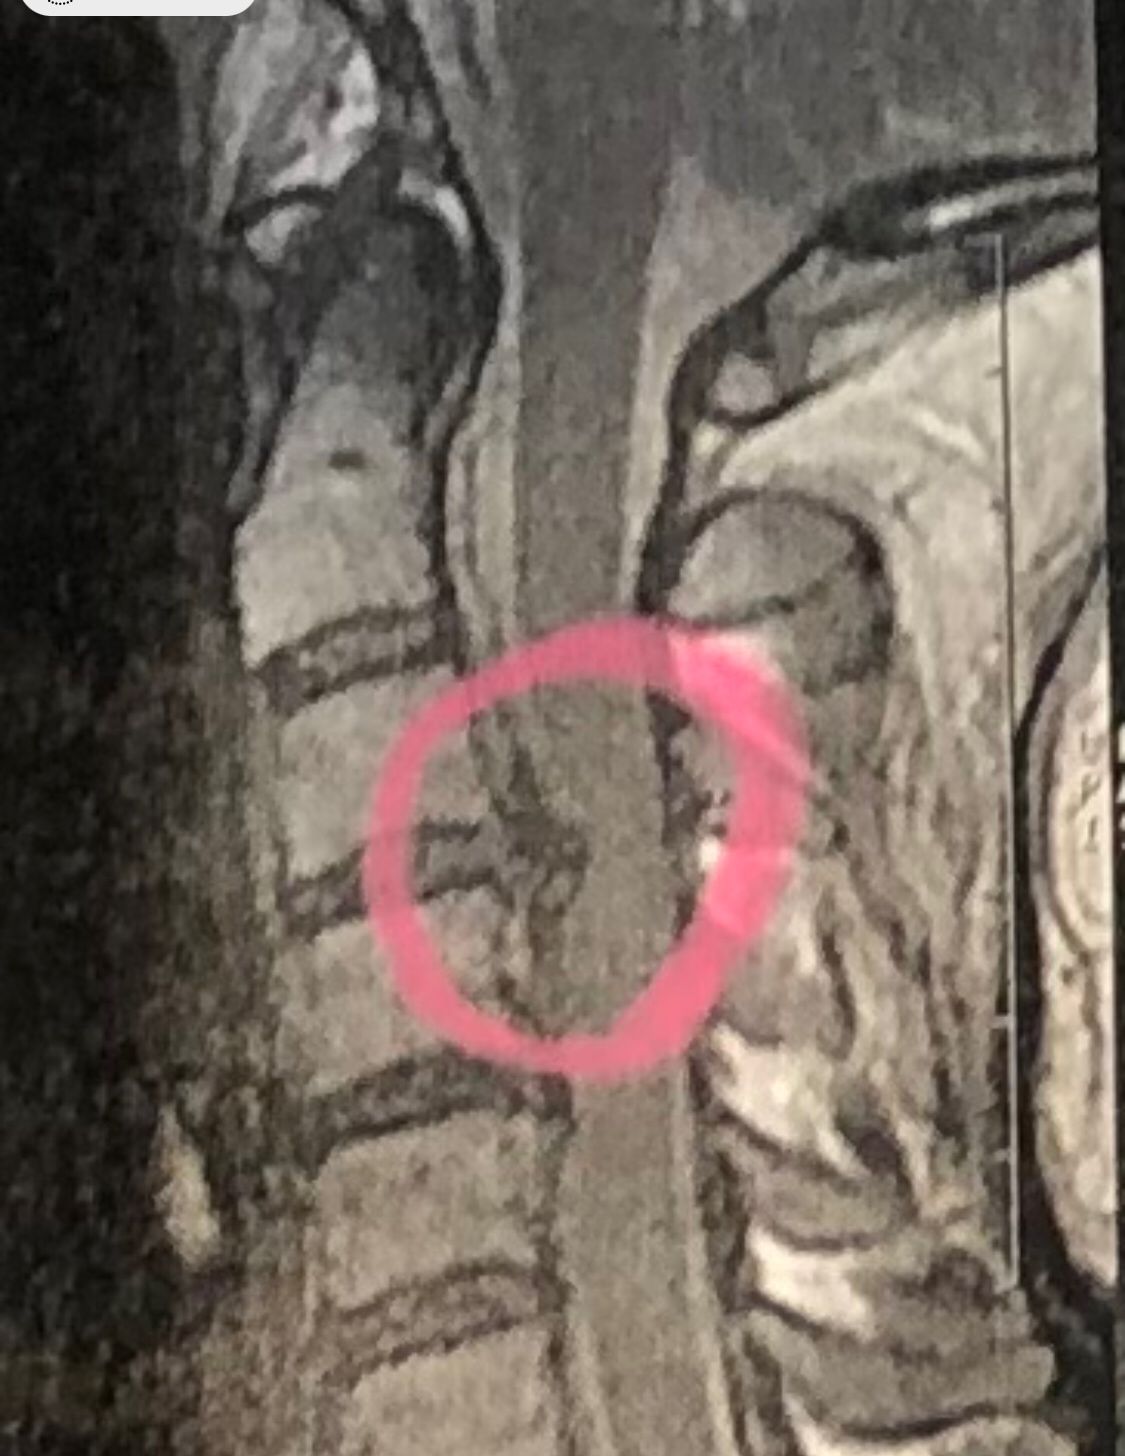

41 years old man presented to my clinic in October 2023 with acute and sever R neck pain with radicular pain to his R upper extremity along C6 dematom since 2 weeks ago. Examination didn’t show any upper motor signs. Was suggested urgent surgery

I ordered EMG/ NCV : showed mild R C6, C7 irritation without any active axonal loss

In his MRI was reported R. para R. IVF Massive extrusion. I decided to control his pain and manage this patient with reevaluation of patient every other session. For 5 sessions i just used acupuncture and laser and IFC and mild adjustments to his R. T3-T7 and mild arthosteem to above and below involved segment. Cervical adjustment considered contraindicated for this patient. From session 6th- 8th i started to use mild/gentle cervical decompression. He used soft cervical collar all the time. His pain decreased by 80 percent

I gave him cervical traction pump to be used 3-5 times per day at home for the next 3 months and i released the patient. He was evaluated every week once for one month and after that every 2 weeks. After 3 month I repeated MRI. Size of the herniated disc was reduced greater than 50 percent. Asked him to do another mri in 6 months

In general: Precise selection of the patients, examination,diagnosis, plan of management, reevaluation and treatment can be done by doctors of chiropractic for the patients with spinal disc herniation and stenosis Moreover giving reasonable time to these kind of patients under direct supervision by their chiropractic doctors can prevent unnecessary surgery. Proper selection of these kind of patients is another important fact that can be done precisely by chiropractors.

MRIs before and after proper management of this patient: